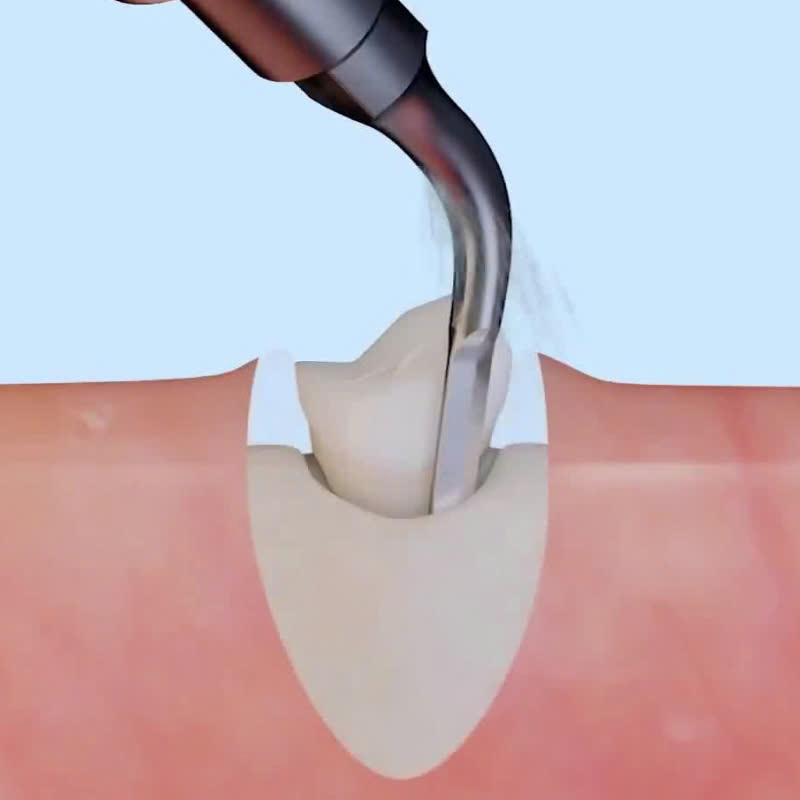

- Sử dụng máy Piezotome: Bác sĩ sẽ sử dụng máy Piezotome để cắt nướu và xương hàm, tách răng khỏi ổ răng một cách chính xác.

- Lấy răng ra khỏi ổ răng: Sau khi tách răng, bác sĩ sẽ nhẹ nhàng lấy răng ra khỏi ổ răng.

- Công nghệ siêu âm: Máy Piezotome sử dụng sóng siêu âm để cắt mô mềm xung quanh răng mà không làm tổn thương đến các mô khác, giúp quá trình nhổ răng sẽ được trở nên nhẹ nhàng hơn.